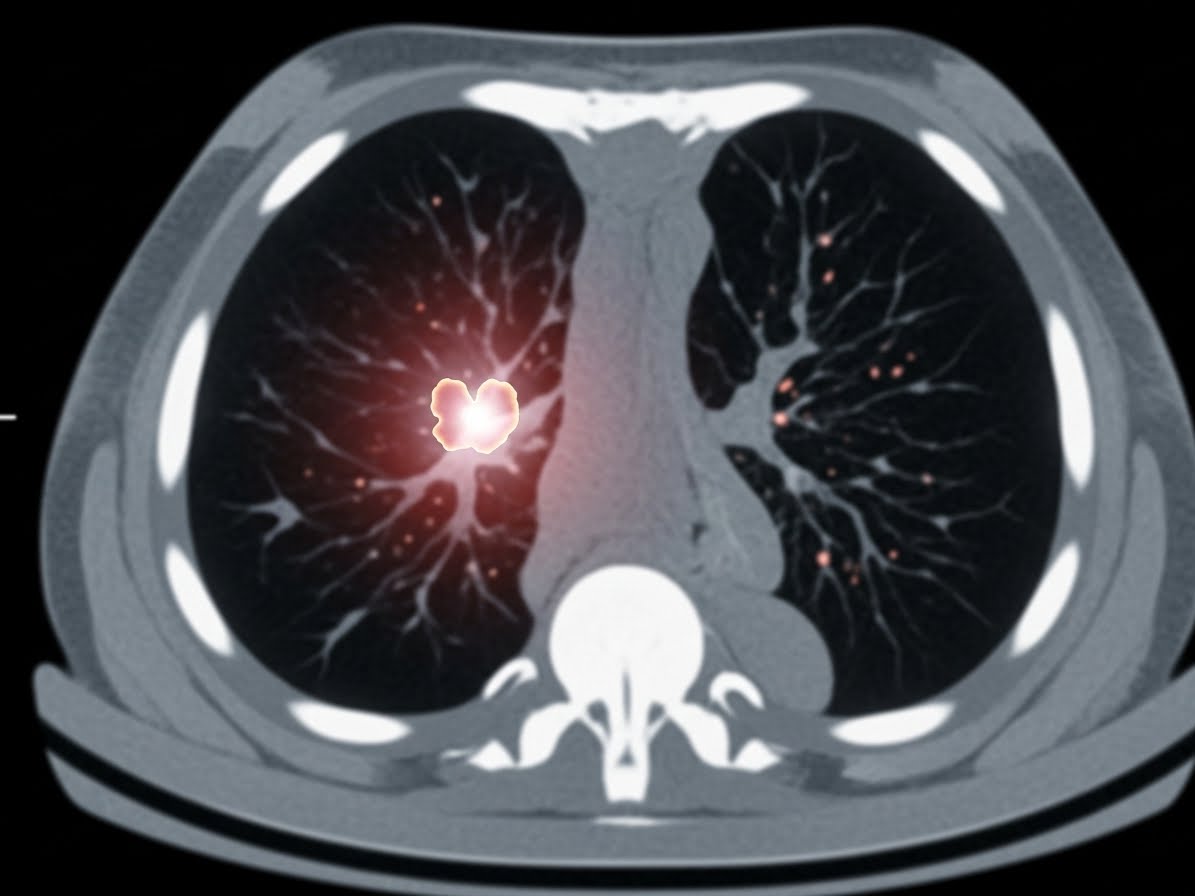

흉부 X-레이에서 이상 소견이 발견되거나, 폐암이 강하게 의심되는 경우에는 추가적인 정밀 검사가 필요합니다. 가장 일반적으로 시행되는 검사는 저선량 흉부 CT입니다. CT는 X-레이보다 훨씬 정밀하게 폐 내부를 들여다볼 수 있어 작은 병변도 놓치지 않고 발견하는 데 큰 도움을 줍니다.

이 외에도 객담 세포 검사, 기관지 내시경 검사, 경피적 폐 생검 등을 통해 암세포의 유무와 종류를 확진하게 됩니다. 이러한 검사들은 다소 불편할 수 있지만, 정확한 진단을 위한 필수적인 과정이므로 의료진의 지시에 따라 적극적으로 임하는 것이 중요합니다.

- 정확한 진단을 위해 흉부 CT, 기관지 내시경 등 정밀 검사를 적극적으로 고려해야 합니다.

A3: 고위험군(장기 흡연자 등)의 경우, 저선량 흉부 CT 검사가 폐암 조기 진단에 가장 효과적인 검진 방법으로 권고됩니다. 일반적인 흉부 X-레이로는 작은 폐암 병변을 발견하기 어려울 수 있습니다. 전문의와 상담하여 본인에게 적합한 검진 계획을 세우는 것이 중요합니다.